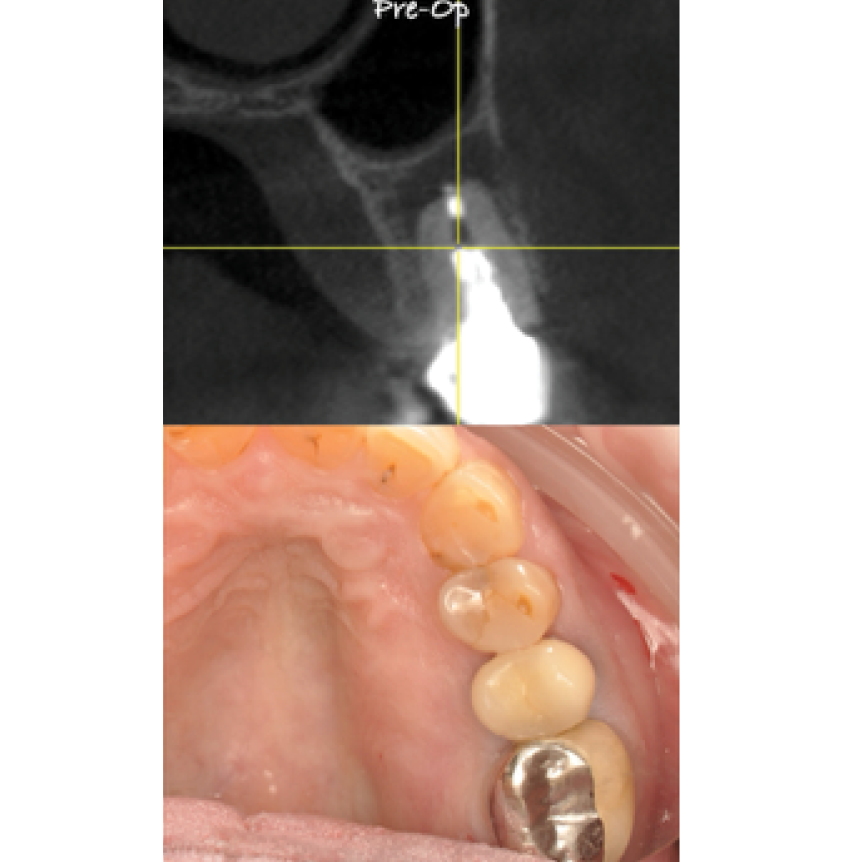

Director’s Clinical Cases

Director’s Clinical Cases